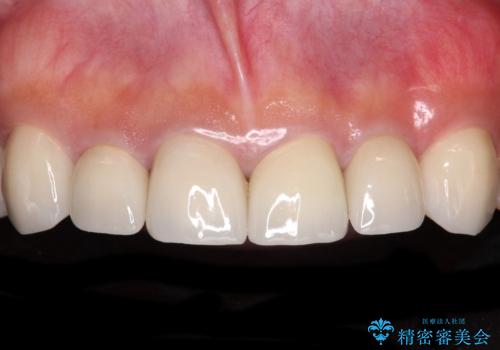

[ 歯が小さい ] 根管治療を伴う矮小歯治療

![[ 歯が小さい ] 根管治療を伴う矮小歯治療の症例 治療後](https://seimitsushinbi.jp/wp/wp-content/uploads/2021/09/80796f663a2a5f8bf47550dede73495e-500x350.jpg?v=1632882140)